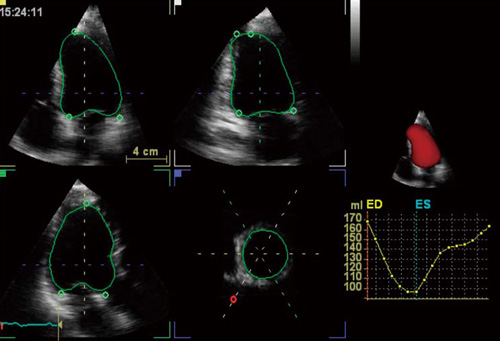

2024年 お歳暮・冬ギフト特集 実践3D心エコー図法 医学一般